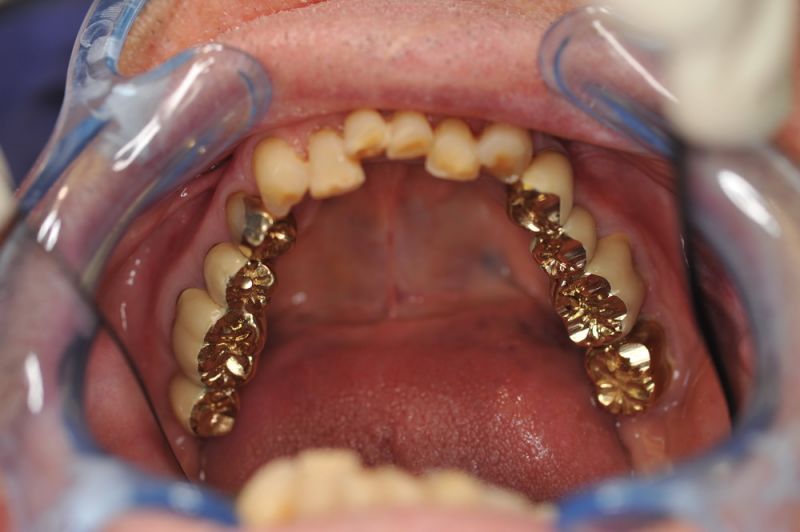

Rekonstruierter Kieler Patient im Recall

Dem Patienten geht es dental gesehen gut.

Die funktionstherapeutische Rekonstruktion befindet sich seit 17 Jahren im Munde des Patienten.

Gemeinsam ist man der Auffassung, dass sich heute zum Glück auszahlt, dass man beizeiten die Fundamente im Mund geschaffen hat, von denen der Patient heute im Alter zehrt.